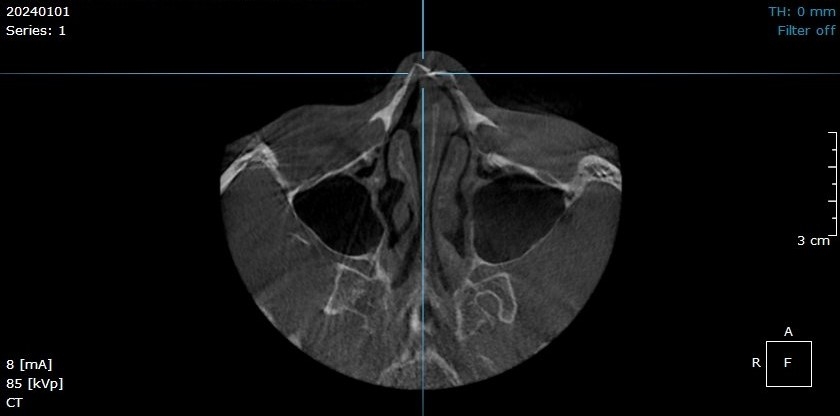

🪻Bệnh nhân bị chấn thương đến thăm khám tại Hồng Hoàng, thông qua hình ảnh chụp CLVT răng hàm mặt dưới đây chẩn đoán bệnh nhân bị gãy xương mũi.